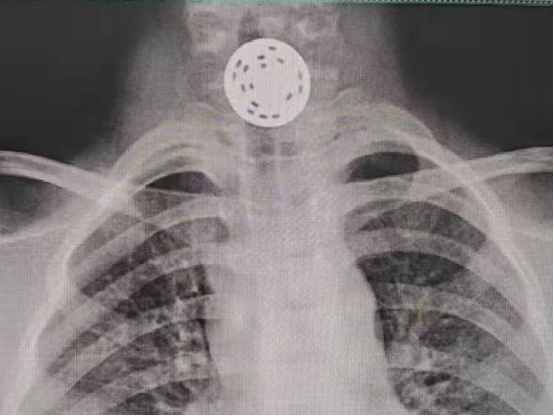

到达医院后,广医一院横琴医院急诊科为小天安排了X光检查。结果显示,游戏币卡在孩子的食管上段,靠近第六、第七颈椎的位置,疼痛明显,情况危急。考虑到孩子年龄较小,食管相对狭窄,耐受差,因此需进行无痛胃镜检查。且由于游戏币长时间卡顿可能会导致食管破损、溃疡,甚至引发穿孔、纵隔感染等严重并发症,所以必须尽快取出异物。

她小心操作异物钳,夹住硬币镂空处,确认夹稳后并未急于外拉,而是轻柔调整胃镜角度,寻找食管最为松弛的状态,缓慢将硬币完整取出。整个过程约15分钟,取出的游戏币直径约25毫米。